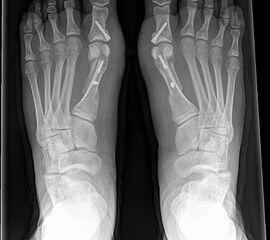

• Hallux valgus interphalangeus (Abb.1, Abb.2)

• Röntgenaufnahme des Fußes (unter Belastung) in dorsoplantarem und seitlichen Strahlengang (Abb. 2a-b).

• Beurteilung des proximalen Gelenkflächenwinkels der Grundphalanx (Proximal Phalangeal Articular Angle, PPAA) sowie des distalen Gelenkflächenwinkels der Grundphalanx (Distal Phalangeal Articular Angle, DPAA) 56 (Abb. 3c und 3d).

• Bestimmung des ersten Intermetatarsalwinkels (IMA, Abb. 3a), des Hallux valgus Winkels (HVA, Abb. 3a), des distalen metatarsalen Gelenskflächenwinkels (Distal Metatarsal Articular Angle, DMAA, Abb. 3b) 7. Möglicherweise muss die Akin-Osteotomie mit weiteren Eingriffen kombiniert werden (z.B.: retrokapitale Osteotomie oder andere metatarsale Osteotomie; Arthrodese).